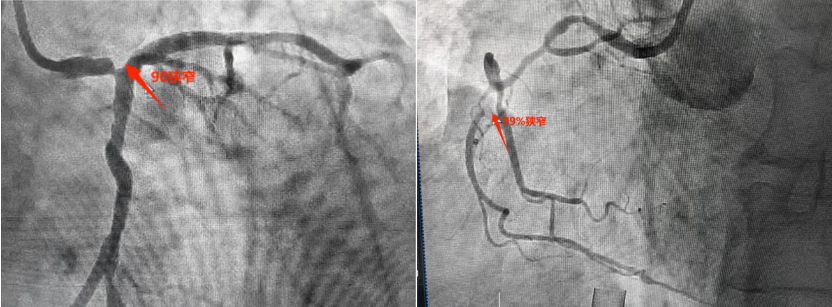

3月7日,西咸院区心内科冠心病介入团队朱舜明副主任医师带领唐治国主治医师、李强强主治医师、张翔住院医师、柳莎莎护士长、崔文宇护师,以及介入导管室团队雷博副护士长、瞿浩主管技师、李炳宇技士,顺利完成物品准备、上机准备、血管评估、穿刺置管等工作,心内科刘博主治医师、梁倩住院医师、刘志远住院医师完成了配血、备血等保障工作,所有医护齐心奋战,整个流程一气呵成,ECMO转机成功。暗红色血液经过膜肺氧合变成鲜红血液,源源不断重返患者体内。术中冠脉造影可见患者左主干末端90%严重狭窄,细小右冠99%狭窄。在ECMO辅助下,心内科介入团队开始进行手术操作。当导丝通过接近闭塞的血管时,患者即出现血流减慢,血压瞬间降至50/30mmHg,透视下心脏几乎不跳动。所有手术人员都捏了一把汗。朱舜明副主任医师迅速指挥抢救,通过提升ECMO转速和流量,并快速用球囊扩张狭窄血管后,患者血流动力学恢复稳定,血压升至110/70mmHg。后续在血管内超声(IVUS)指导下,历时1小时余,完美完成了左主干血运重建。观察患者生命体征平稳后,撤除ECMO并缝合动静脉伤口,体表仅留下不到2cm的痕迹,患者术后胸痛症状明显好转,安返病房,监测生命体征平稳。

介入治疗前造影